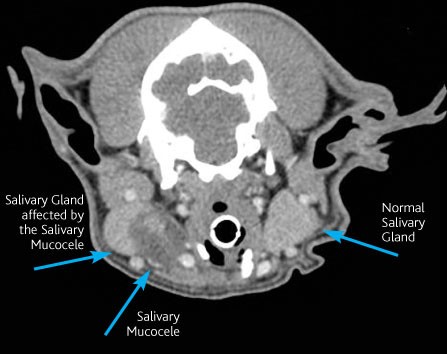

Romeo had a CT scan of his head and neck to highlight which tissue the swelling was associated with. He also had a needle biopsy of the lump whilst he was sedated. The CT scan showed a close association of the swelling to one of his salivary glands and when the needle sample was performed, a large amount of saliva was obtained. This confirmed the diagnosis of a salivary mucocele.